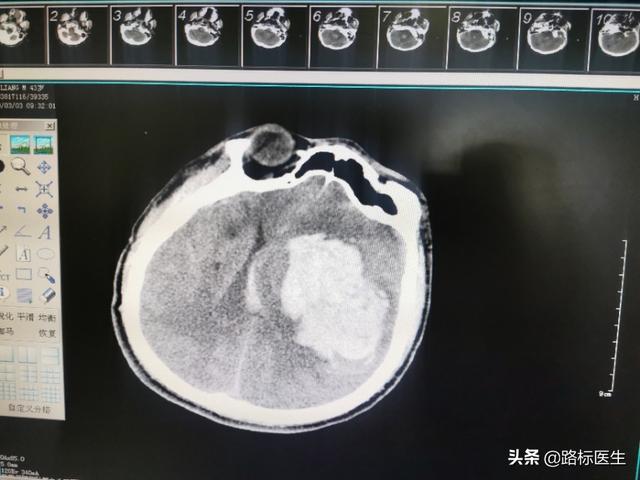

A.これは43歳の男性患者で、私の友人でもあるラオ・チェン、5年来の高血圧症で、最高血圧は180/100mmHgに達したが、血圧は160/90mmHg程度で不快感はなく、最高血圧の時だけ少し頭の腫れを感じ、降圧剤を服用すると血圧が下がり、頭の腫れも緩和される。以前は外来で2種類の降圧剤を併用して治療を受けており、普段からメッセージや電話で血圧を尋ねていたが、コントロールは良好だという。しかし、今年3月、大量脳出血で当院のICUに入院し、脳出血後そのまま昏睡状態に陥り、血圧も呼吸状態も良くなかったため、蘇生術で一命を取り留めたが、まだ目覚めていない。その後、恋人と連絡を取ったところ、最初の数年間は降圧剤を常用しており、血圧も140/90mmHg程度にコントロールされていたが、ここ2年ほどは薬を飲むのが面倒だと思い、自分で降圧剤を止めていたこと、普段は血圧を測っておらず、頭重感があるときだけ血圧を測り、血圧が180/100mmHg程度になっていたこと、一度だけ降圧剤を食べ、頭重感が良くなってから薬を飲むのを止めたことなどを知った。そして、短気で、タバコを吸い、酒を飲み、徹夜でトランプをし、コントロールできない家族、誰もコントロールする勇気がない。

頭部CTスキャンで右大脳基底核領域の脳出血が示唆され、心臓モニターに表示された血圧は190/130mmHgであった。